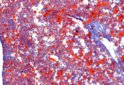

普魯士藍染色 Prussian blue stain